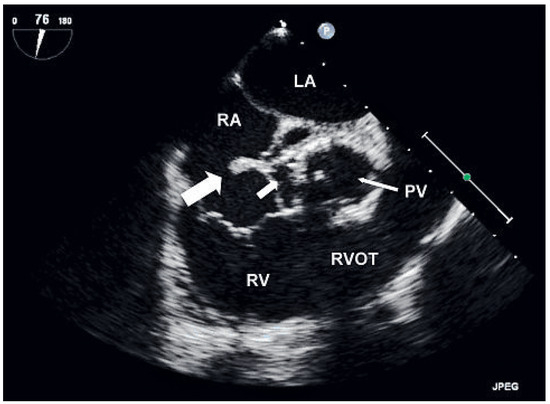

Background: Cardiac resynchronisation therapy (CRT) has become a mainstay in the treatment of patients with severe heart failure mainly due to large clinical trials demonstrating a reduction in morbidity and mortality. The aim of the present study wa...